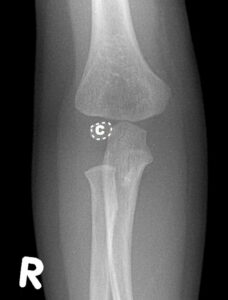

[toggle title=”Radiokapitellar Hat” state=”close”]

AP, Lateral ve Oblik grafilerde radius başının ortasından geçecek şekilde çekilen çizgi kapitulumun ortasından geçmelidir.

Bu hat üzerinde herhangi bir sapma radius başı çıkığını düşündürür. Bunun dışında lateral kondil kırıklarında da bu hat üzerinde bozulma görülebilir.

Radiokapitellar Hat Kapitulumun medialinde kalmış